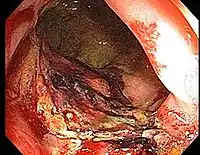

Chronic radiation proctitis

- Chronic Radiation Proctitis

- Timing: 9-14 months after RT, but sometimes after 2 years (and as late as 30 years)

- Etiology: obliterative endarteritis and chronic mucosal ischemia, leading to progressive epithelial atrophy and fibrosis. Ultimately, development of a chronically ischemic intestine prone to fibrosis and bleeding

- Symptoms: diarrhea, obstructed defecation (if strictures), bleeding, rectal pain, rectal urgency, and fecal incontinence. Rarely fistulas, SBO

- Diagnosis: colonoscopy, barium studies if suspecting strictures and fistulas

- Endoscopy (Argon plasma coagulation) - benefit for bleeding